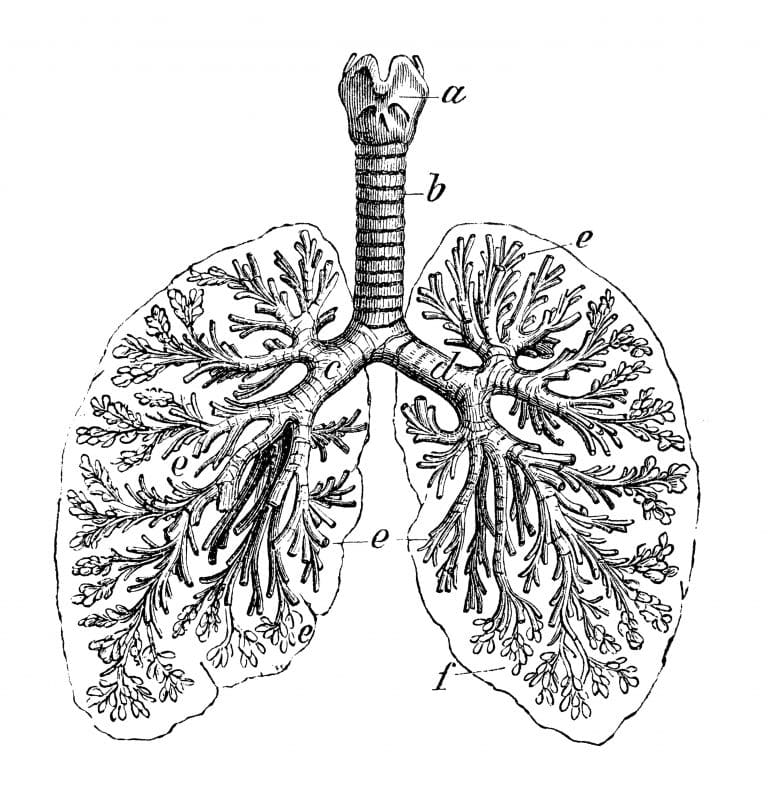

Illustration de l’arbre bronchique.

La maladie pulmonaire obstructive chronique (MPOC), aussi appelée bronchopneumopathie chronique obstructive, est un terme générique qui regroupe les affections caractérisées par une obstruction chronique et irréversible de la circulation de l’air à l’intérieur des poumons. Les symptômes principaux sont un essoufflement (ou manque d’air) qui s’aggrave peu à peu, et une toux chronique avec production de crachats. La MPOC est malheureusement une maladie évolutive pour laquelle il n’y a pas de traitement curatif, et elle représente la quatrième cause de décès dans le monde.

En fait, ce diagnostic inclut les bronchites chroniques et l’emphysème. « Il est possible d’être atteint d’une des deux maladies ou des deux à la fois. Elles sont la plupart du temps dues à l’utilisation du tabac [NDLR : dans 80 % à 90 % des cas] », explique l’inhalothérapeute Marie-Ève Girard. La pollution atmosphérique ainsi que les poussières et les produits chimiques sur le lieu de travail sont également des facteurs de risque.